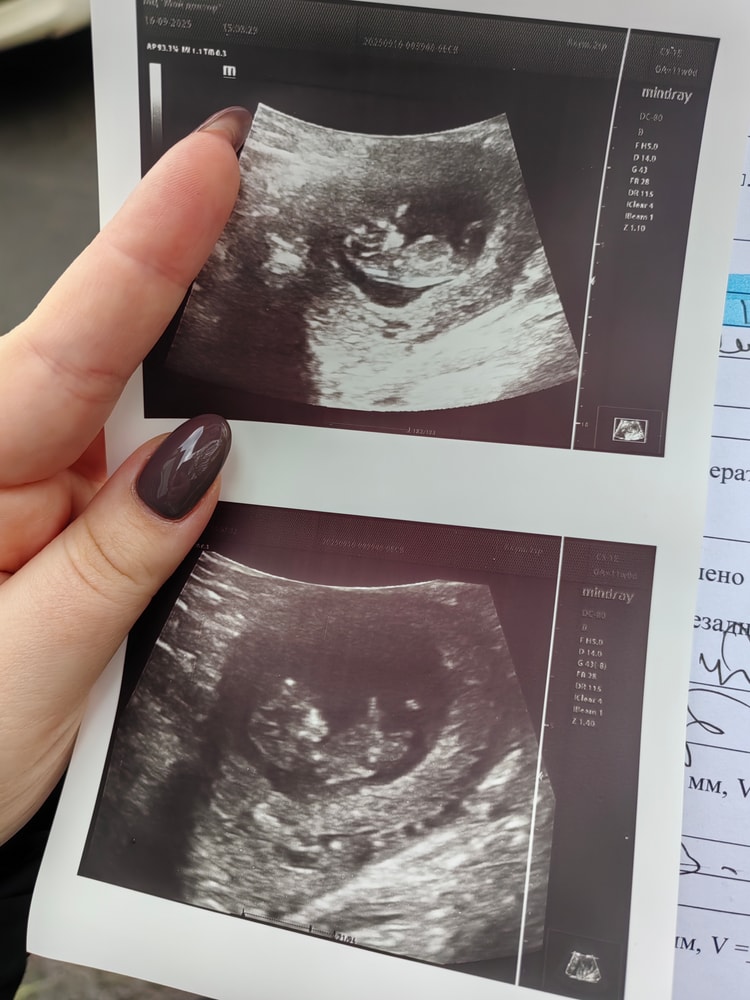

В общем, все хорошо. Растем, уже бултыхаемся, ручку под голову положил(а) 🥹

Ктр крошечки 39мм, чсс 150 уд/м

Соответствуем сроку 10н5д. А по месячным 11 ровно, но ничего, разница малюсенькая